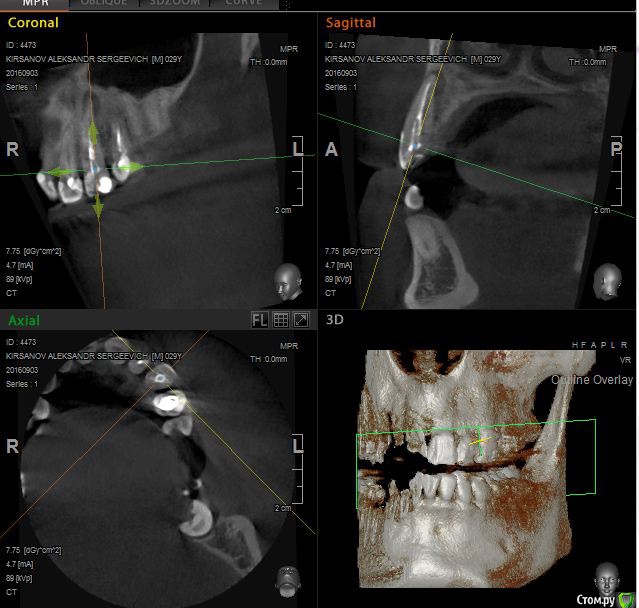

St. Опубликовано 12 ноября, 2016 Поделиться Опубликовано 12 ноября, 2016 Выложу скрины приложенного КТ. Так ответов будет больше. Есть пропущенный канал в 6 зубе. И нужно проверить на жизнеспособность соседний 7. Я бы рекомендовала попробвать перелечить и понаблюдать. Но Вы должны для себя понимать что перелечивание каналов очень сложная, дорогая и непрогнозируемая процедура. Хотя вероятность успеха достаточно высока. Если хотите гарантий - тогда удаление и имплант как восстановится кость. Еще хорошо бы знать как давно лечили каналы в этом зубе, как он вел себя после лечения, беспокоит ли сейчас? 2 Ссылка на комментарий

St. Опубликовано 12 ноября, 2016 Поделиться Опубликовано 12 ноября, 2016 11, 21 по кт без особенностей. Так что артефакты скорее всего. В 23( левый клык) есть тоже воспаление на корне. Нужно планово перелечиавать. Ссылка на комментарий